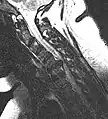

L'imagerie par résonance magnétique peut montrer la hernie, le canal vertébral, les nerfs, les tissus environnants. Les tissus mous sont les mieux analysés par cet examen qui est le plus performant pour le diagnostic de hernie discale. Les images pondérées en T2 montrent clairement la hernie.

IRM lombaire sagittale montrant une hernie discale de niveau L4-L5.- IRM lombaire sagittale montrant des protrusions discales.